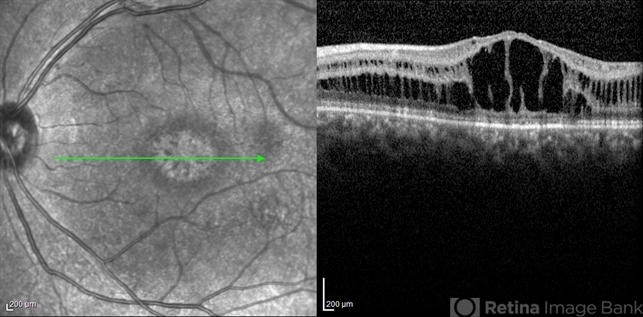

- optical coherence tomography (OCT), juvenile retinoschisis, macular schisis

- Shabnam Pooreh, Negah Eye Center, Tehran , Iran

Optical coherence tomography system

Specteralis - Description

- OCT image of the left eye of a 30-year-old man with juvenile retinoschisis. VA OS is 20/100.